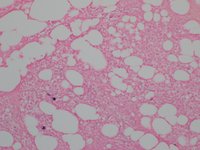

Category: Lymphoma: Mature B-cell and Plasma cell Neoplasms > Low-grade B-cell lymphoma > Lymphoplasmacytic lymphoma

CD138 positive plasma cells are arranged singly and in small clusters. The background shows CD138 negative hematopoetic cells.